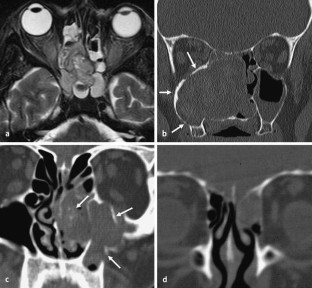

Abb. 1